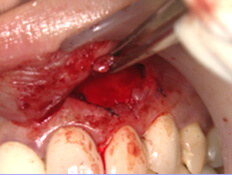

症例5. エムドゲイン

| 骨が無くなってしまっています。 | 再生を促す薬です。 | 薬を塗布した後すぐ縫合。 |